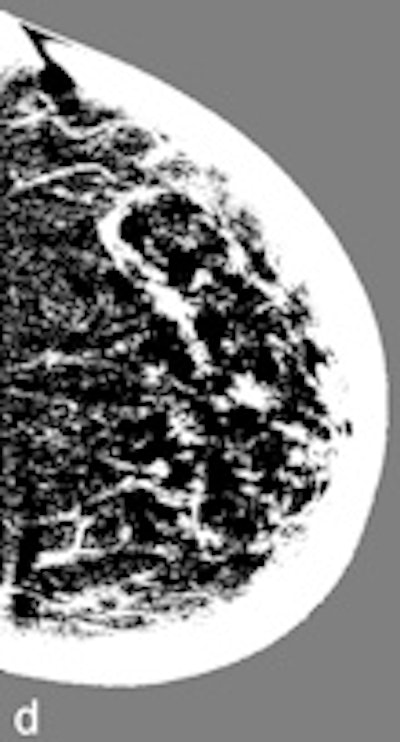

Another example of a finding in a left-sided craniocaudal view that was reported clearly more often by radiologists when using premium view (PV). A: Tissue equalization (TE) processed image. B: PV processed image with the annotation. C: Similar to image above, the resulting image of subtracting TE from PV. D: The thresholded version of C.For all six radiologists, perceived case suspiciousness -- defined as the highest probability of malignancy of all radiologist findings -- was higher using premium view optimization.

The major difference between the processing algorithms was an additional local contrast optimization when premium view was applied. "Premium view is aimed at increasing the visibility and suspiciousness of malignant lesions, but in our study the perceived suspiciousness of benign lesions and normal cases is increased as well," the researchers wrote. "An effect of local contrast enhancement could be that both normal (dense) structures and abnormal structures appear more suspicious due to their enhanced signal."

High-contrast images are usually preferred because of the increased visibility of the lesions, but the algorithm also affects normal cases. "In our study, the perceived suspiciousness of the normal cases increased even more than that of the malignant cases," they noted.